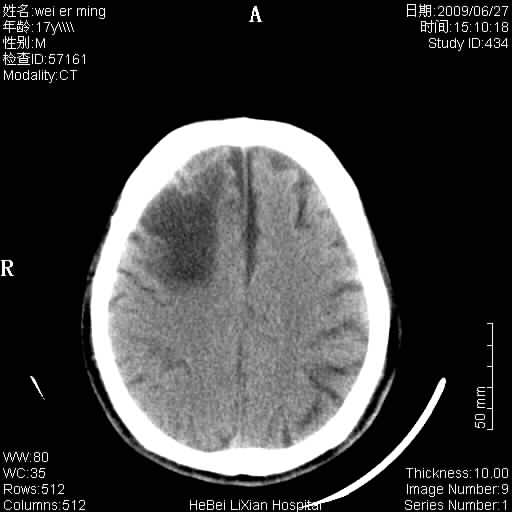

标题: CT20838:帮忙看看,是软化灶吗?

患者,男,67岁.既往有脑血栓病史.若是软化灶里面怎么出现钙化呢?

周围没有水肿,没有占位;结合病史考虑为软化灶,钙化。